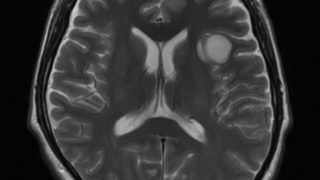

今日は手術入院の前日。ゴールデンウイーク前の4月に検査のため2週間ほど入院していたので2ヶ月ぶりになります。その時の様子は別途まとめておこうと思ってます。簡単に自分の病気の説明をしておくと、グリオーマ(GLIOMA:神経膠腫)という脳の実の...